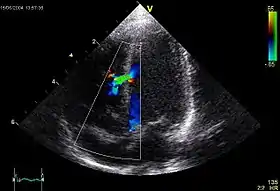

اکوکاردیوگرافی (به انگلیسی: Echocardiography) یا پژواکنگاری قلب[1] که به آن "سونوگرافی قلب" یا "اکوی قلب" هم گفته میشود روشی غیر تهاجمی است که با استفاده از امواج صوتی، ساختمان داخلی قلب به تصویر کشیده میشود و در حقیقت به عنوان استاندارد تشخیص بیماریهای قلبی تلقی میشود.[2]

در این روش از سونوگرافی استاندارد دو بعدی ، سه بعدی و داپلر برای ایجاد تصاویر از قلب استفاده می شود.[3]

اکوکاردیوگرام نه تنها می تواند تصاویر سونوگرافی از ساختارهای قلب ایجاد کند، بلکه میتواند با استفاده از سونوگرافی داپلر ارزیابی دقیقی از خون جریان یافته به بافت قلب ایجاد کند. داپلر رنگی و همچنین داپلر طیفی برای به نصویر کشیدن هرگونه ارتباط غیر عادی بین دو طرف چپ و راست قلب ، نشتی خون از طریق دریچه ها (نارسایی دریچه ای) و تخمین میزان باز بودن دریچه ها (یا باز نشدن آنها) استفاده میشود.